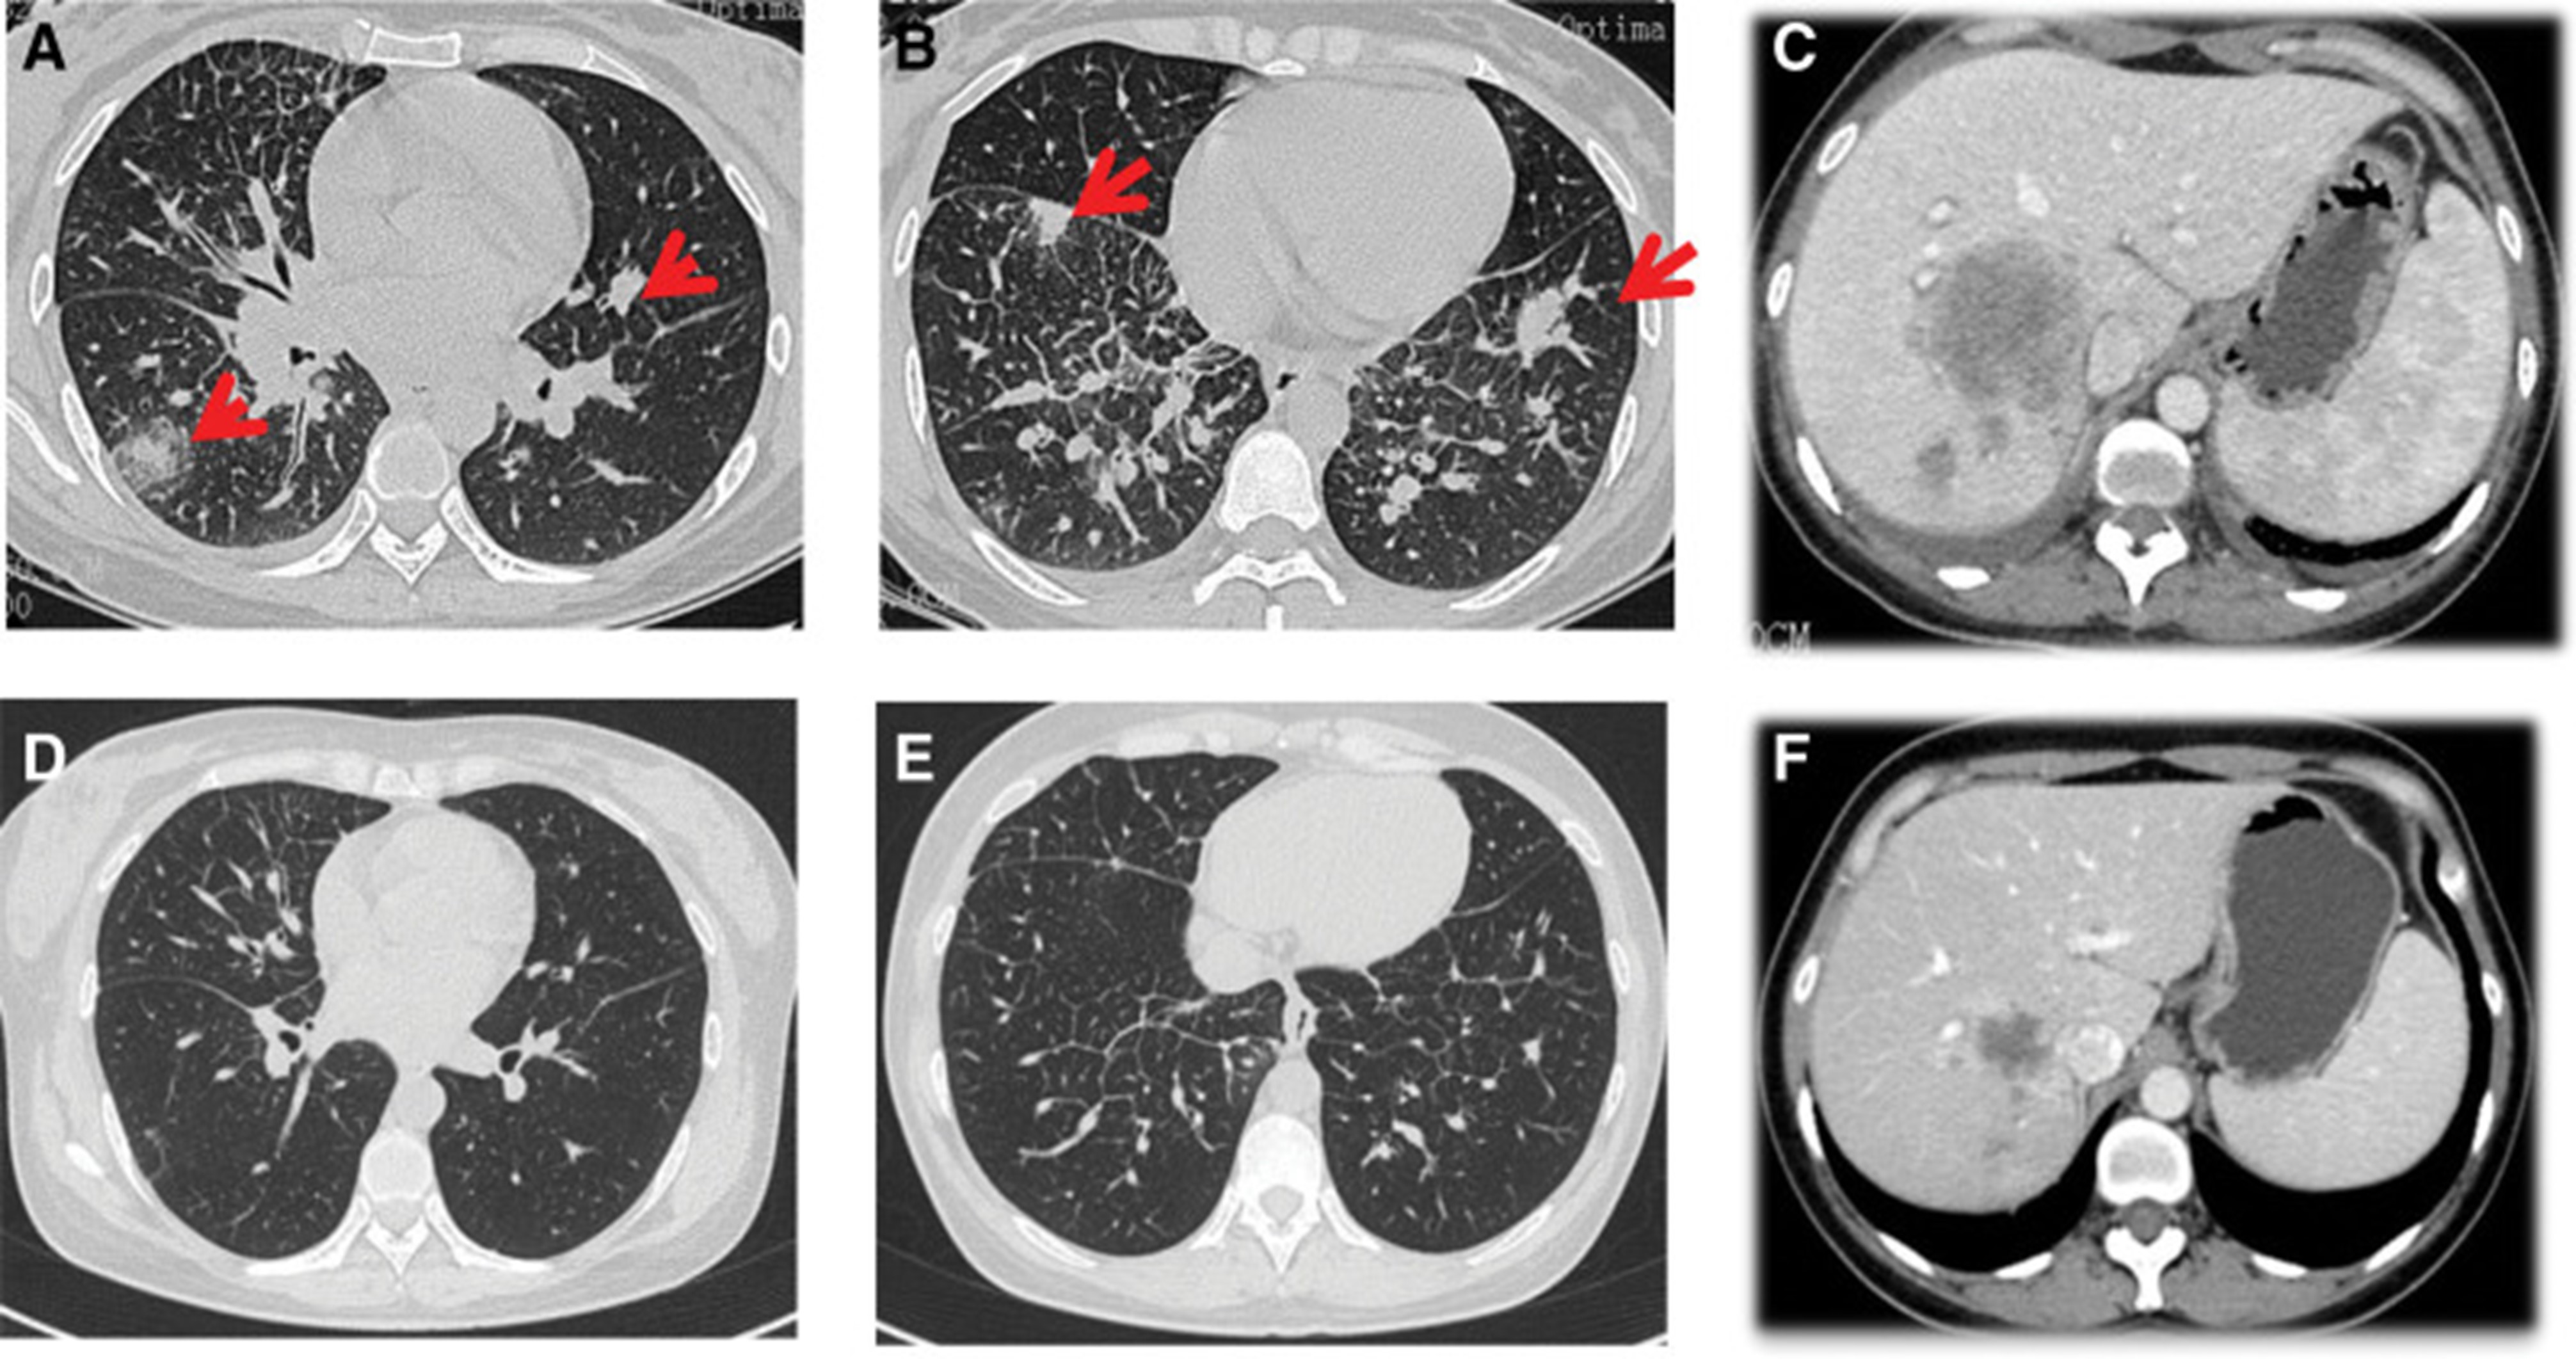

2020年4月,患者胸部CT示“双肺多发结节,纵隔及肺门多发肿大淋巴结;附着于肝右叶,略呈低密度肿块影”(图 1)。(图4A,4A、B)和腹部CT显示“肝脏多发肿块”(图1)。(图 4C)。骨扫描显示“身体多个部位的骨代谢异常增强”。2020年4月19日,对“右肝肿块和右锁骨上肿块”进行活检,病理指征(右肝肿块抽吸、右锁骨上肿块抽吸)为低分化腺癌。结合免疫组化结果,首先考虑的是肺腺癌转移。最终诊断为“IV期肺腺癌伴多发肝和骨转移”。基因检测显示“EML 4-ALK 融合,PD-L1 肿瘤阳性细胞数TPS 80%”(图 2)。(图1和和2)。

和 2020 年 6 月 (D-F).jpg)

图 4:2020 年 4 月 (A-C) 和 2020 年 6 月 (D-F) 的 CT 扫描。CT = 计算机断层扫描。

2020年5月1日,患者开始口服艾乐替尼靶向药物进行治疗,2020年6月25日复查,确定治疗效果为PR(部分有效)(根据RECIST1.1)显示肺病灶和肝转移灶明显减少(图1)。(图 3D-F)。2020 年 8 月 27 日复查确定治疗效果为疾病进展(PD, progressive disease),根据 RECIST1.1显示肝脏病变变大(图 1)(图 4A-D)。进行了第二次肝活检,随后的病理学显示“(肝)低分化癌,结合免疫组织化学分析考虑肺腺癌转移”。组织活检进行了第二轮基因检测,结果显示“BRAFV600E 14.79%,EML 4-ALK fusion 14.47%”(图 1)(图 5)。2020年9月20日,对患者我以为用恩沙替尼联合达拉非尼靶向治疗。治疗开始后,患者出现明显发热、寒战、乏力和厌食。期间患者左侧出现大量胸腔积液,胸腔积液中脱落细胞为“非典型细胞,考虑为腺癌”。随后,该患者接受了 1 次胸腔内铂输注。

和 2020 年 8 月.jpg)

图 5:2020 年 6 月(A 和 B)和 2020 年 8 月(C 和 D)的 CT 扫描。CT = 计算机断层扫描。